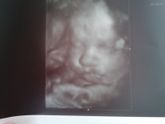

И тут решила , что хочу хоть мельком увидеть малыша , и совместила так сказать полезное с приятным ) конечно самое главное что все хорошо, кровотоки супер , ребёнок полноценно готов жить вне меня ) осталось только дождутся когда же ) ну и конечно же … Читать далее